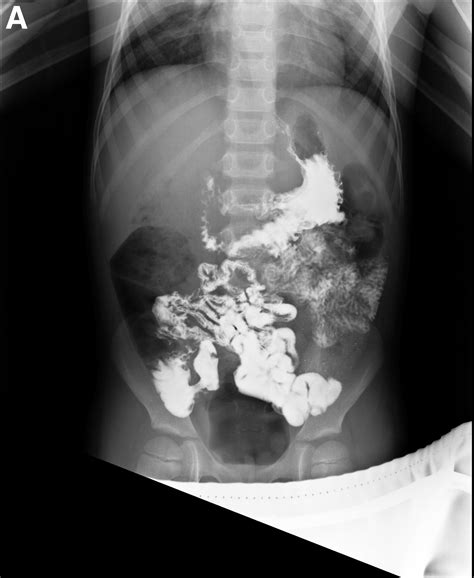

• Barium Ingestion: The patient drinks a barium solution, which coats the lining of the small intestine and makes it visible on X-rays.

• X-Ray Imaging: A series of X-rays are taken at regular intervals as the barium moves through the small intestine. This process can take several hours, depending on how quickly the barium passes through the digestive system.

• Positioning: The patient may be asked to change positions to help the barium move through the small intestine and to capture different angles.

During the procedure, it is important for the patient to remain still during each X-ray to ensure clear images. The healthcare team will monitor the progress of the barium and adjust the timing of the X-rays accordingly.